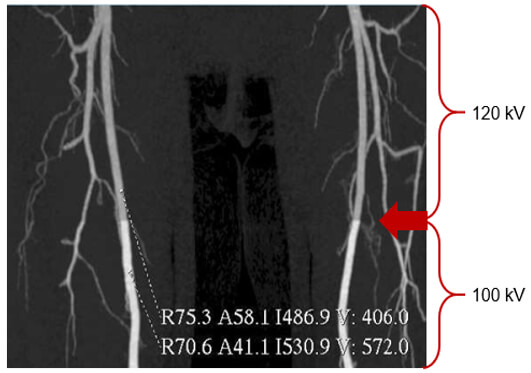

The choice of x-ray tube voltage affects the image contrast. Low kV values mean higher contrast or few shades of gray, more black and white, while high kV values are selected when acquiring images with low contrast or one that requires seeing many shades of gray.

Higher kVp means that the photons have higher energies and can penetrate thicker objects.

This image shows the effect of the kVp on image contrast. Note the differences between 100 and 120 kVP. The higher the kVp, the lower the contrast, known as low contrast resolution.

Low contrast detection is used to examine structures with low contrast such as the brain or the abdomen. This is accomplished by using higher kVp.